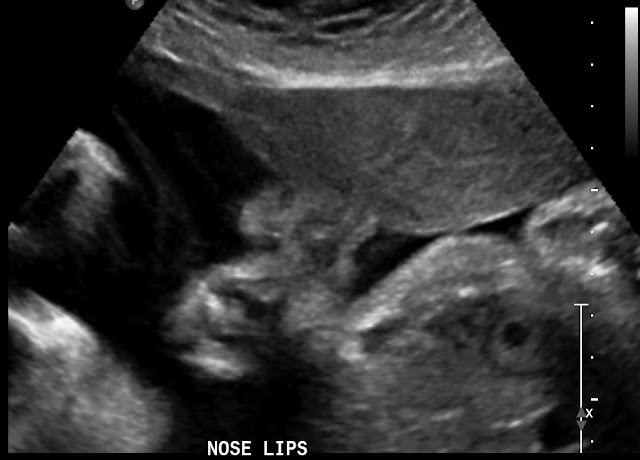

According to my last ultrasound at 19 weeks, today I am 32 weeks and 5 days. However my midwife sent me to have another ultrasound today to check on the size of the baby, according to today's ultrasound I am 34 weeks and 4 days, which would make my due date March 8th, instead of the 20th... She also measured about 5 lbs. 4 oz. The ultrasound tech said either my due date is wrong, or I will have a very big baby. The midwife gets the results of the ultrasound by the end of the day, and I'm anxious to know if she will be changing my due date or not! My next appt. is not until my 36 week appt, and from there I go every week, however, if the most recent ultrasound is correct I will be almost 38 weeks along then! I told Weston regardless if they change my due date or not, I want to be prepared and have everything ready just in case... Also, we were told that she is in a breech position, traverse breech... I'm terrified of a c-section, but I'm not worried about it yet, I think she still has plenty of time to move head down! Here are a few pictures of baby girl :)